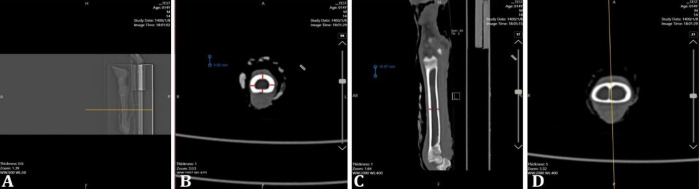

Bone structure has been widely studied in mammals, however, osteon structure in sheep has received relatively little attention, especially in terms of its location on the forelimbs and hindlimbs. The aim of this study was to investigate the histometric characteristics and mineral composition of the metacarpus and metatarsus of adult Sanjabi sheep. Metacarpal and metatarsal bones were collected from five adult Sanjabi sheep (n = 10). Morphometric measurements were performed on computed tomographic scan images. Histometric parameters were measured on histological sections. The mineral composition of the bone samples was detected using the X-ray fluorescence method. The diameter of the Haversian canal in the right metatarsus was significantly greater than that in the other bones. The smallest diameter of the Haversian canal was observed for the right metacarpus. The diameter and area of the osteons in the right metacarpal were significantly greater than those in the other bones. The amount of essential mineral elements was not significantly different among bones. Aluminum and lead were significantly greater in the left metatarsus. The highest amount of copper was observed in the left metacarpus. These results indicated that there was a greater load on the right limb. This compensatory mechanism might be used to put more weight on the right forelimb and reduce the pressure caused by the weight of the rumen on the left forelimb. However, to prove this hypothesis, more detailed and extensive studies are needed in the future.